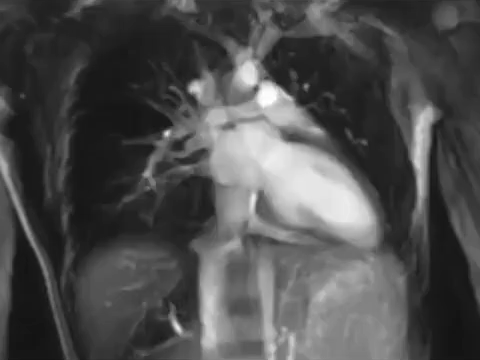

5. Kolorizovaná 3D snímka aorty z magnetickej rezonancie